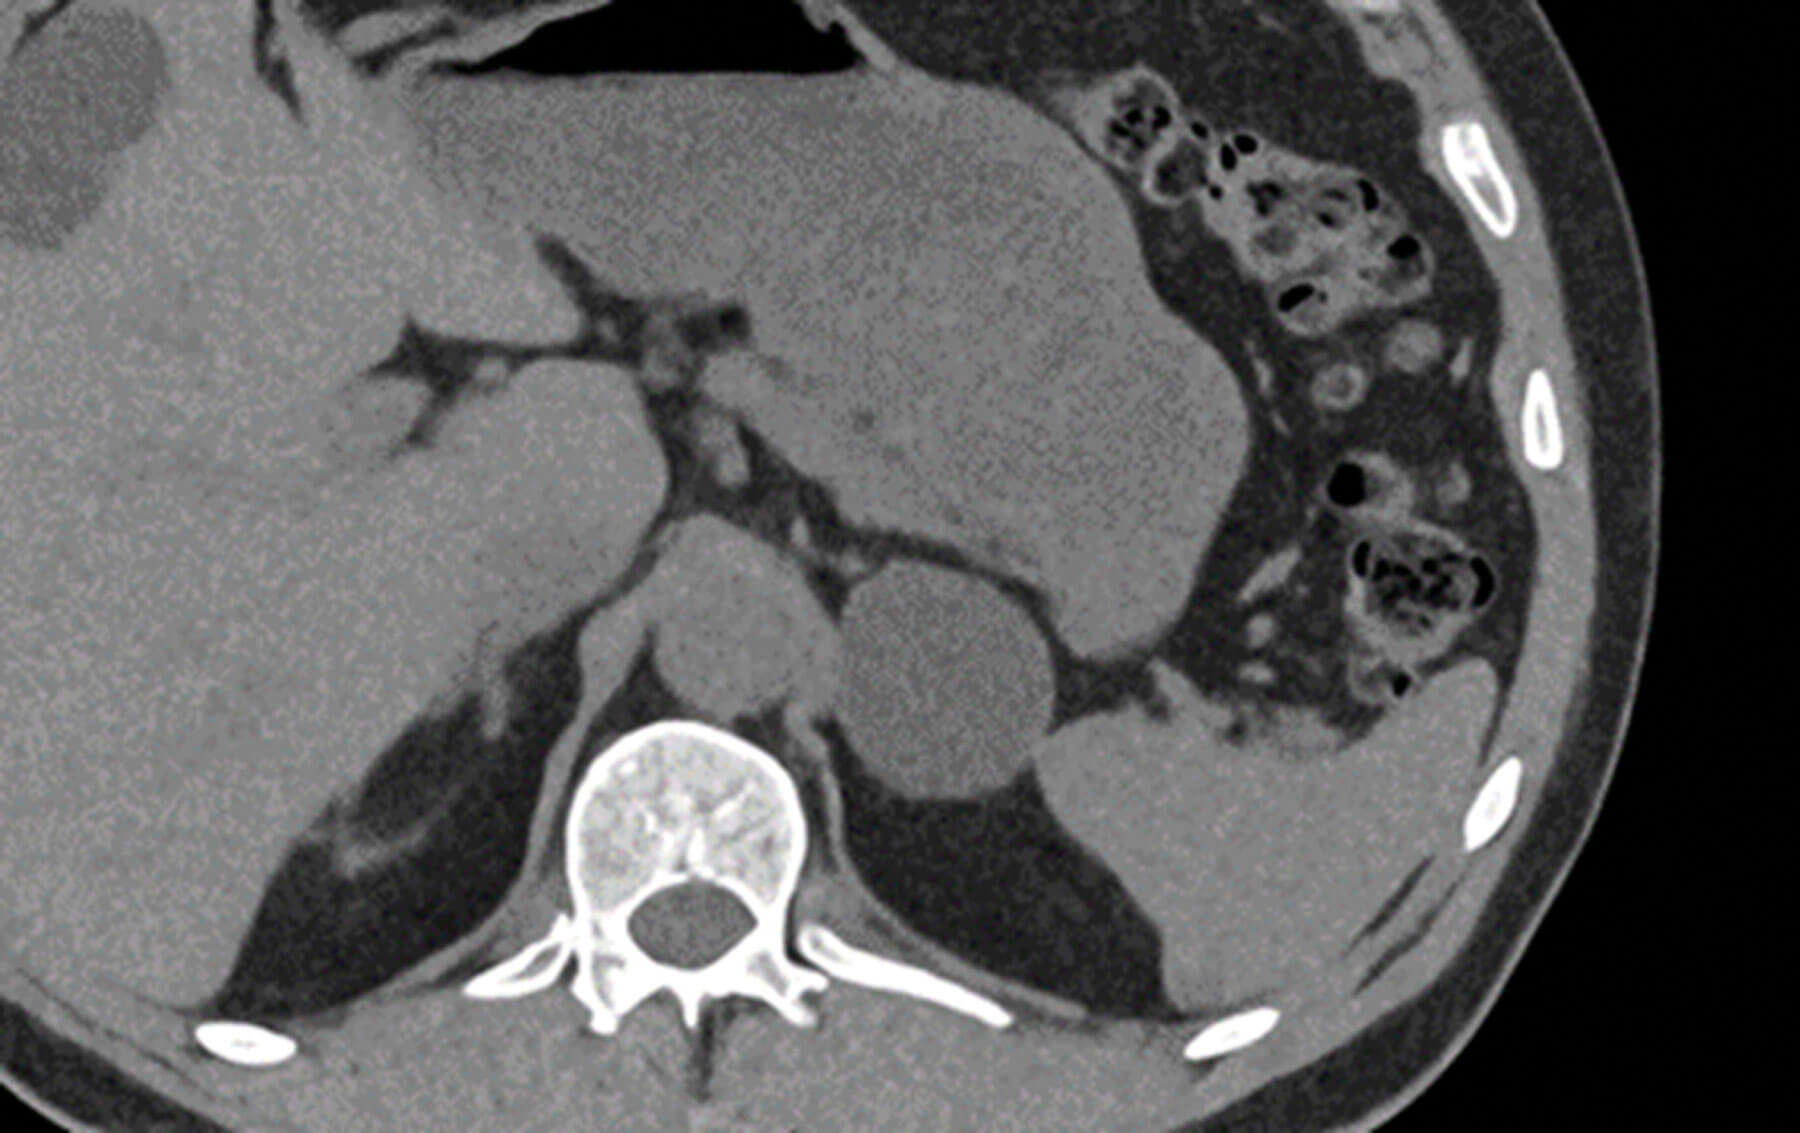

Figure 2: Axial non contrast CT. The left adrenal gland shows a well circumscribed uniform low attenuation mass (CT density -2HU) consistent with a benign lipid rich adrenal adenoma.